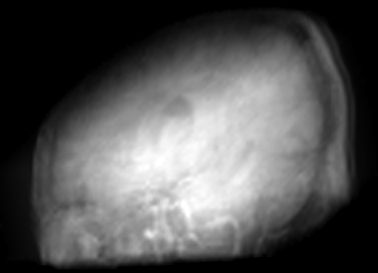

Figure 2: Inputs and outputs of the guided filtering pipeline based on the WDSR network. T1 & T2 MRI pairs (a)-(e) and CT & MRI projection images (f)-(j).

In Fig. 2 and 4, exemplary input, output and label images of the pipeline are presented for both tasks. Additional super-resolved images for both network architectures with and without the guided filter can be seen in Fig. 3. The results show a consistently high quality over both, the tomographic and the projective domain, as well as both tasks. Corresponding quantitative evaluation can be found in Table I and II. For SR, the WDSR network, i.e., the designated super resolution network, performs consistently better for both datasets with and without the guided filter. Applied to the tomographic images, the approaches without the guided filter deliver slightly better quantitative results. For the projection images this difference diminishes and both approaches are on par. In the case of denoising, the approaches with the guided filter deliver a lower mean absolute error while the structural similarity is increased without it. Though, the measurable differences are only marginal. The results generated by the plain guided filter without the learned guidance map are numerically worse than the approaches empowered by the guidance map generator for all tasks. This observation is most prevalent when observing the results of the tomographic T1 and T2 Flair images for SR, while for denoising the results are closer to the deep learning-based approaches.

In general, the decrease in image quality metrics w.r.t. to smaller radii is much stronger for the tomographic T1 and T2 Flair images than for the projection images. We assume the reason for this to be the difference in resolution of both datasets. The projection images resemble the ground truth more closely from the outset when compared to the tomographic images as seen in Fig. 2(b) and 2(g), respectively. Consequently, more information has to be generated by the networks. As the guided filter is sensitive towards correlation between the input and guidance map the constraints on the applicable changes are more severe.